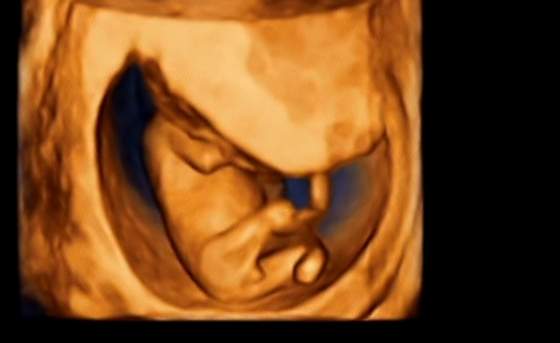

też w 15 tc byłam na usg 4d, były to pierwsze prenatalne. Lekarka powiedziała, że nikomu nie mówi o płci na tym etapie bo to jak wróżenie na tym etapie. Sama jak była w 3ciej ciazy to w 15 tc widziała dziewczynke, kobieta która jej robiła usg też widziała dziewczynkę a za 2 tyg okazało się ze chłopak

wiec nic nam nie powiedziała.

za 2 tyg jak bylismy na usg u mojej juz lek. to dzidziok zakrywał się ręką albo ustawiał tak, że nie bardzo było widać. Powiedziała, że chyba dziewczynka bo jak miała okazje przez 2 sek tam zajrzeć przeloem

to nic nie widziała, żeby na chłopakla wskazywało. No więc ja muszę jeszcze poczekać